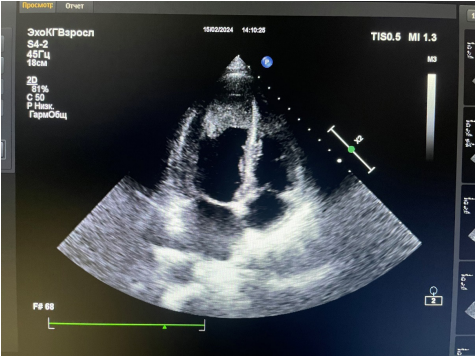

Рис. 1. Фото трансторакальной ЭхоКГ от 15.02.2024. Апикальная позиция.

Поступление в гематологическое отделение городской больницы (13.02-15.02.2024). Стернальная пункция: в миелограмме бласты 0,6%, эозинофилы 45%. Эозинофильный лейкоз исключен. ЭхоКГ (15.02.2024): лоцируется разрастание эндокарда, выстилающее верхушку ЛЖ с переходом на передне-боковую стенку размерами 36×36 мм с поражением задней створки МК, разрастание эндокарда в полости ПЖ у верхушки — ЭЛ? Гипокинез верхушки с незначительным снижением ФВ ЛЖ 53%. Недостаточность МК III степени (объем ЛП 38 мл), трикуспидального клапана II степени. Признаки умеренной легочной гипертензии, СДЛА 38 мм рт.ст. Пограничный гидроперикард (рис. 1, 2) |